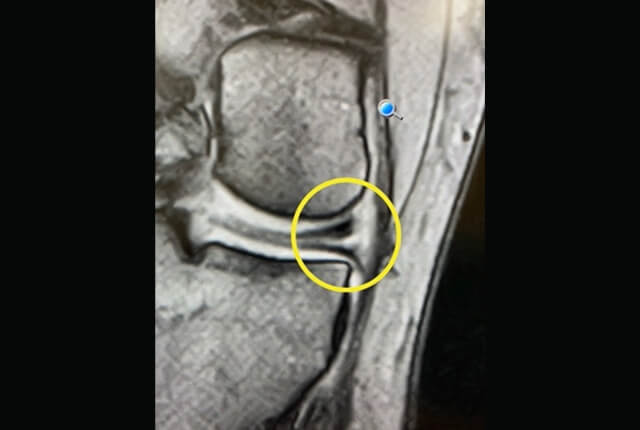

• MRIでACL損傷や半月板損傷を確定診断

診断1

診断2